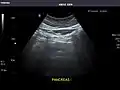

Pancreas: Visualized portions unremarkable.